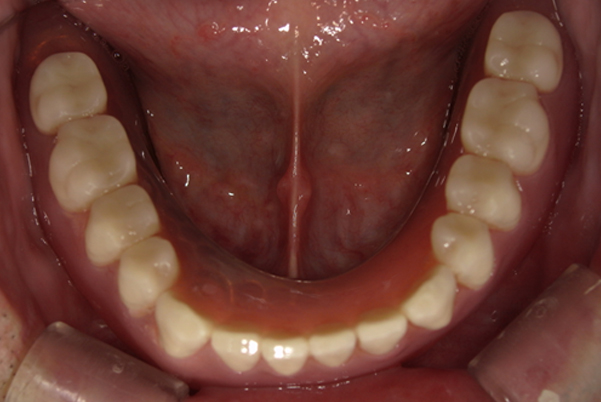

下顎治療前

-

下顎治療後

治療前の入れ歯の奥歯は、治療後の義歯と比較しても分かるように、歯が削れ平らになった状態です。

これにより奥歯のかみ合わせは低くなり、前歯のみが強くあたり、かみ合わせにより上の前歯大きな負担がかかっていたことにより、上の前歯が折れたことが考えられます。